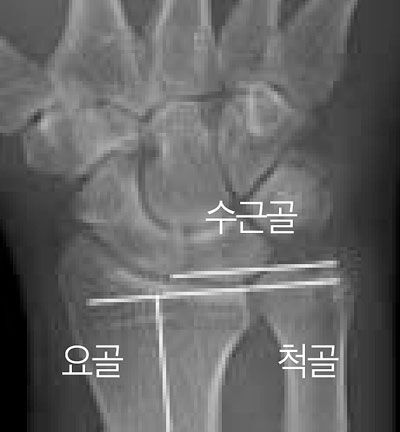

손목에서 새끼 손가락 쪽의 척골의 길이가 요골보다 긴 경우, 척골과 수근골(손바닥뼈) 사이에 충돌이 일어나 연골이 닳고 통증이 생기는 현상이 '척골충돌 증후군'이다. /중앙대병원

척골충돌 증후군은 팔뚝을 구성하는 두 뼈 중 하나인 새끼 손가락 쪽에 위치한 척골이 안쪽의 요골에 비해 긴 경우 잘 발생한다. 손목을 쓰는 동작이 반복되면, 튀어나온 척골과 손바닥 뼈가 충돌하면서 그 사이의 삼각 섬유연골이 닳아서 통증이 생긴다.